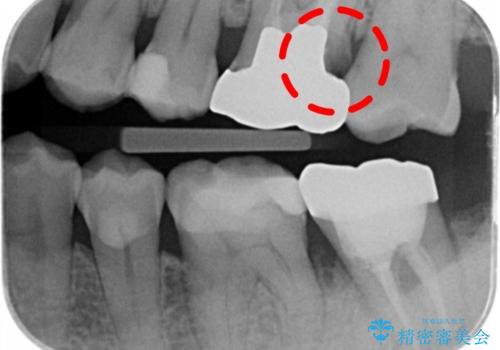

検査で見つかった虫歯 セラミッククラウンでの治療

- 検査の結果被せ物の下に虫歯が確認された患者様です。

虫歯を取りきった後セラミッククラウンでの修復処置を行います。

被せ物の裏側の虫歯は被せ物を取らないと除去できません。

今回は過去に治療された部分をすべてやり直しました。